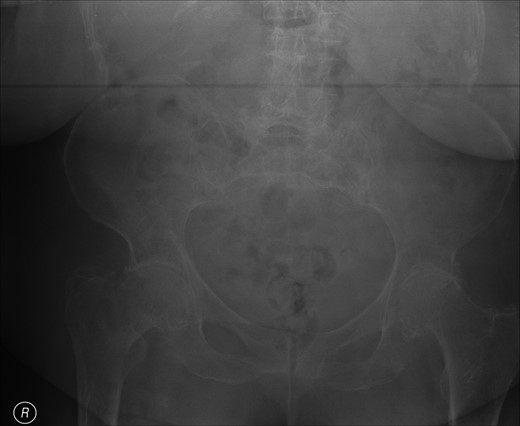

Post-operative nausea delayed immediate attempts at rehabilitation. Although she sat out in a chair, transfers were accomplished with a hoist. At 10 days, post-operatively she was transferred to a peripheral hospital, where rehabilitation commenced with a 2-min period of standing with support. The following morning she complained of greatly increased pain in the operated hip. A radiograph showed that the screw had separated from the barrel, as shown in Fig. 3.